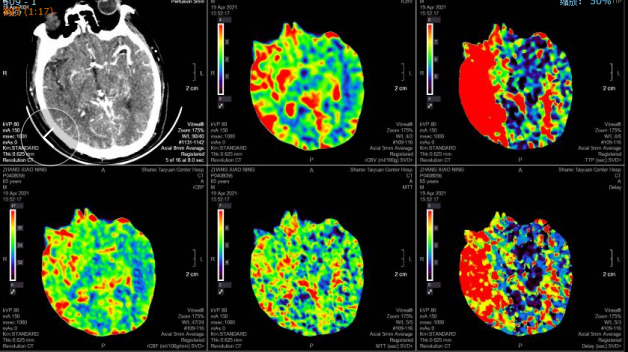

CTP:

右侧基底节区、颞叶、顶叶低灌注区域。

术后影像:

术后8天头颅CT及CTP影像:无出血,右侧半球脑灌注较术前明显改善。